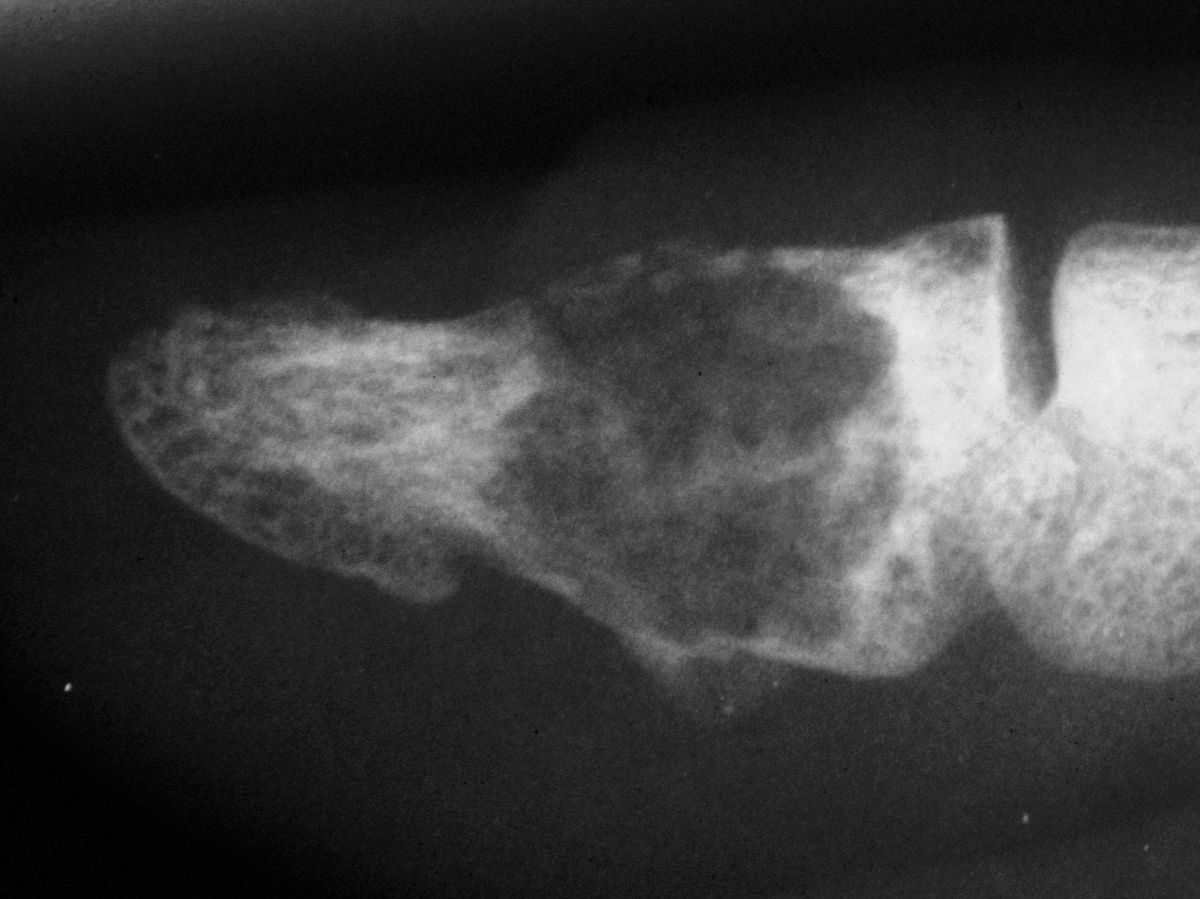

| Case 1. This patient presented with pain with thumb pinch and a sense of fullness in the thumb pulp. Plain radiographs demonstrate an expansile, geographic, radiolucent, juxtaarticular intraosseous mass, typical for an enchondroma. There is circumferential cortical thinning and possible cortical breaks. |

| Because the palmar cortex appeared to be the strongest remainig area, a midlateral approach was chosen over a midline volar longitudinal incision. |